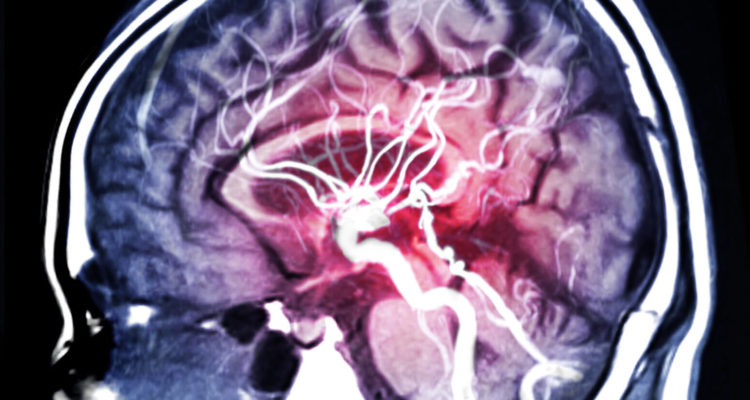

11.11.2025 15:07Як знизити ризик інсульту та деменції: користь чаю та кави для людей у віці